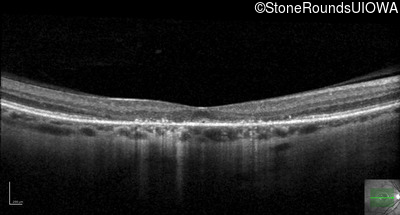

Optical Coherence Tomography - Right - 5/700

Exemplar / OCT Stack

Optical Coherence Tomography - Left - 20/125